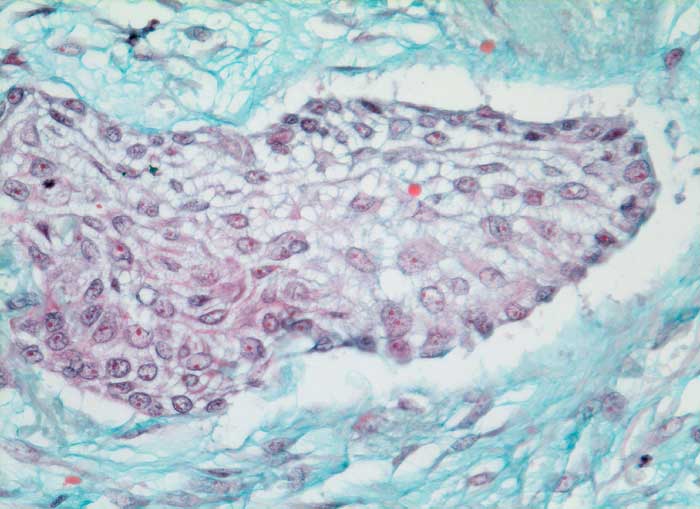

PathoPic ID 6341 - mässig differenziertes Plattenepithelkarzinom

mässig differenziertes Plattenepithelkarzinom

maligner Tumor

Lunge

Solider Tumorzellverband ohne erkennbare Verhornung. Die Desmosomen zwischen den Zellen sind sehr gut erkennbar. Reichlich desmoplastisches Stroma.

Histologie

320